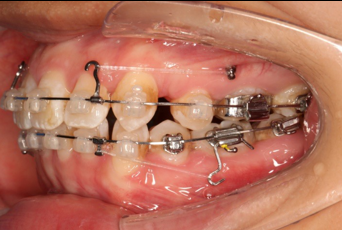

2016.10.31  初戴,0.013cu-niti2017.1.13  上颌加TPA,U56间斜形植入韩国庆北1312-08种植钉,上下0.16cu-niti

2017.02.16  上下0.014*25 cu-niti,50g 拉尖牙远中

2017.04.28

2017.04.28  上0.016*25ss 13、23近远中约5度 v形曲,下0.017*25ss

2017.05.26  磨牙近中倾斜,下颌36、46加power arm

2017.07.25

2017.07.25  上前牙加颈部弹力线